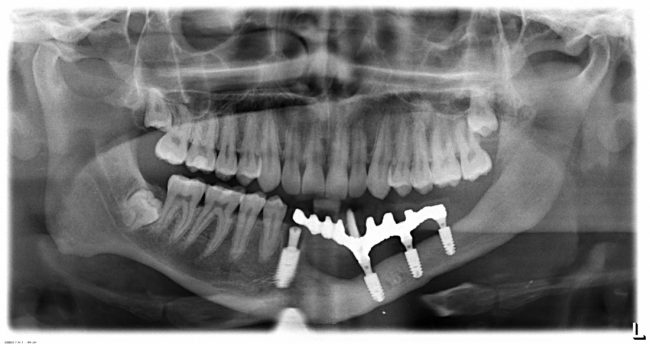

После фиксации опорных балок мы сделали обычный для таких случаев контрольный снимок для оценки посадки. Как обычно, всё выглядит прекрасно — не зря же я заметил, что мы не экономим на зубных техниках и лабораториях!

Установка зубного протеза